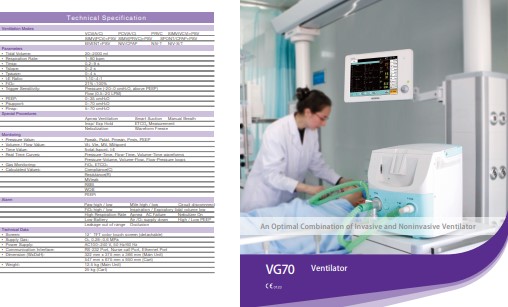

Medical

SGTI Flex COVID-19

SGTI Flex COVID-19

COVID-19, speedy and sustainable community spread even without identifying exactly who and how to spread.